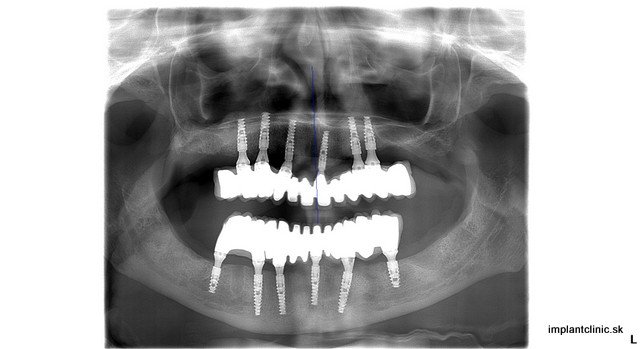

Na kompletnú rekonštrukciu Pavlinho chrupu bolo potrebných 24 extrakcií, 12 zubných implantátov, 2 x sinus lift, 12 implantátových koruniek v sánke a 12 implantátových koruniek vo vrchnej čeľusti. Zdravie našich zubov ovplyvňuje naše celkové zdravie, ale aj kvalitu nášho života. Pokazené zuby nie sú len estetický problém. Prepojenie medzi stavom chrupu a našim zdravím je oveľa väčšie, ako si myslíme. Zápaly v ústnej dutine sa krvnou cestou dostávajú do celého tela a môžu spôsobiť ďaľšie problémy. Odkladanie návštevy zubného lekára môže spôsobiť to, že zuby sa pokazia natoľko, že o ne prídeme. Tým sa zmení aj kvalita nášho života. Bezzubá čeľusť je vážny estetický nedostatok, ktorý si všimneme na ľuďoch hneď ako začnú rozprávať.

Naša pacientka Pavla mala ešte všetky svoje zuby, no tie z hľadiska dlhodobej prognózy už nebolo možné ponechať. Preto boli všetky zuby extrahované. Hneď po extrakcii sa na vrchnú čeľusť a sánku zaviedlo po 6 zubných implantátov. Implantáciu vykonal náš hlavný implantológ MUDr. Marek Salka.